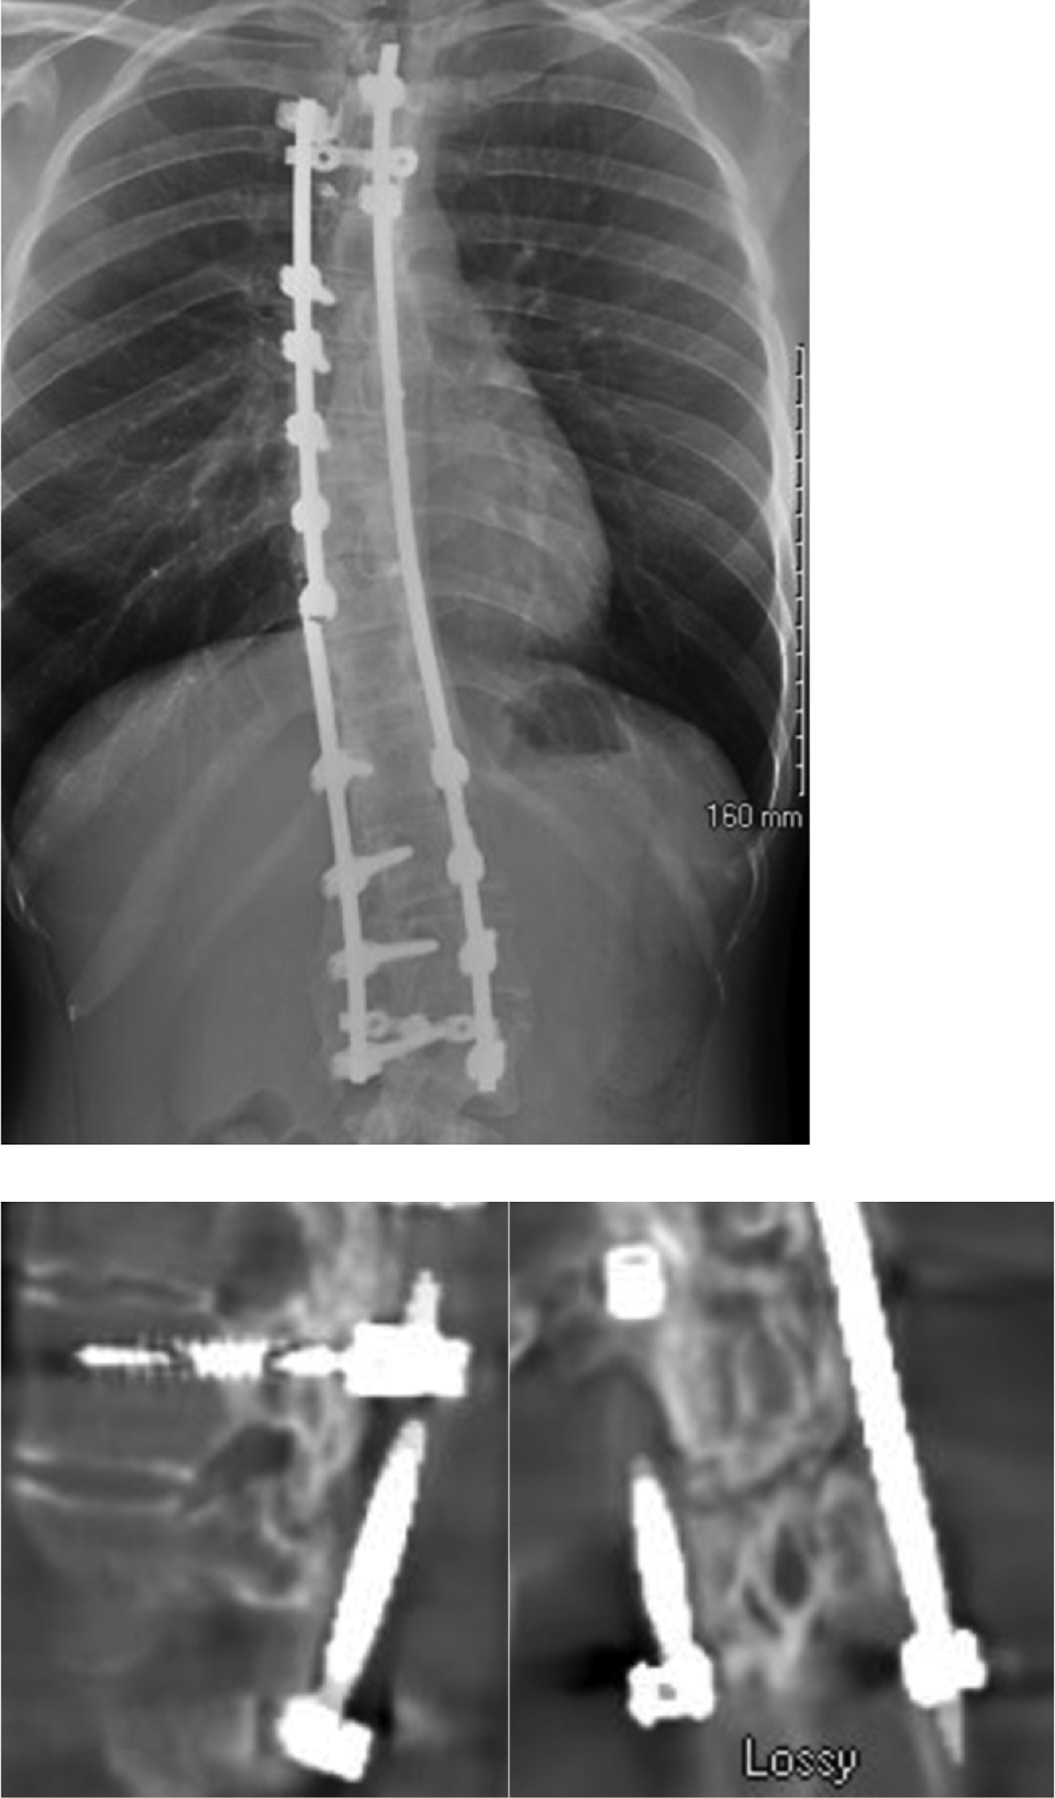

A review of pedicle screw complications in pediatric scoliosis surgery found that 4.2% of screws were mal-positioned (Figure 3), based on any breach of the pedicle. However, in studies where CT scans were obtained on all patients, the rate of screw malposition increased to 15.7%. Among the studies reviewed, the reported rate of revision surgery for mal-positioned screws was only 0.83%.17

Figure 3. In addition to more severe risks, the mal-positioned screw on the left may be a pain generator. The patient on the right had canal compromise that led to 9 months of severe neuritic pain.

jposna20220030_fig3.jpg

In a study of 120 patients undergoing PSF for AIS, pedicle screw loosening was more likely at the upper instrumented vertebra (UIV) or the lowest instrumented vertebra (LIV) compared to other vertebrae.18 Mal-positioned screws can cause pain perhaps due to direct contact with neural elements or inadequate fixation leading to excess motion.